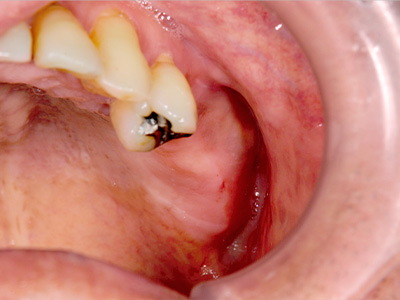

40代女性。上顎の右前歯が差し歯になっていたのですが、歯の根の先の部分が腫れを繰り返し歯根の破折も考えられるとのことで、抜歯してインプラントかブリッジかと説明されたそうで、インプラント治療を希望されて当院に相談に来られました。

CTでみると、歯の根の外側の薄い骨がなく、ここに炎症を起こすと症状の改善は難しい状態でした。

抜歯してインプラントということで了承され、抜歯即時インプラント埋入も考えられたのですが、歯の根の状態、骨の状態を考えて、抜歯して治癒を待ってインプラント埋入をすることとしました。 -

抜歯して5か月経過後にCT撮影すると非常に良く治癒していましたが、骨の厚みが4mm程しかありませんでした。

そこで、インプラント埋入と同時に外側に人工骨と自家骨を混合して補填し、人工の膜(メンブレン)で覆うという、骨の厚みを造成する手術(GBR)を併用しました。 -

手術後のCTです。

うまくインプラント埋入、骨造成ができていると思います。